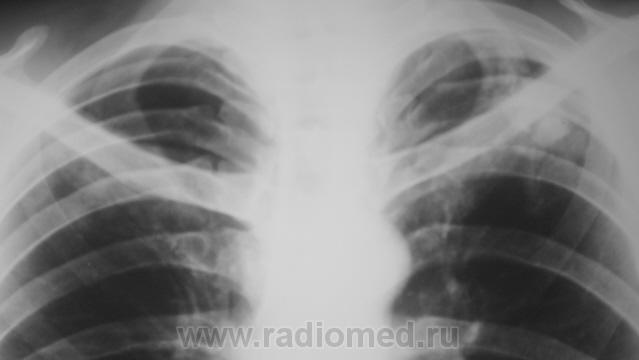

Пациент на учете. Направлен фтизиатром, как «клиническое излечение».

Конгломеративная туберкулома для фтизы уже считается пустяком.

А если они множественные?

На мелкие туберкуломы,судя по тактике фтизиатров, можно закрыть глаза.

Следовательно, "клиническое излечение"?

Вернее, наверное, будет сказано "стадия ремиссии". Неизвестно, когда такая туберкулома может "бахнуть". Особенно, если она по типу "заполненной каверны".

Конгломератные каверны образуются обычно вследствии инфильтративного tbc, опасности тут поменьше...

Это клиническое отреченение! Оставлена мина замедленного действия. Торакальным хирургам надо работать даже через « не могу».